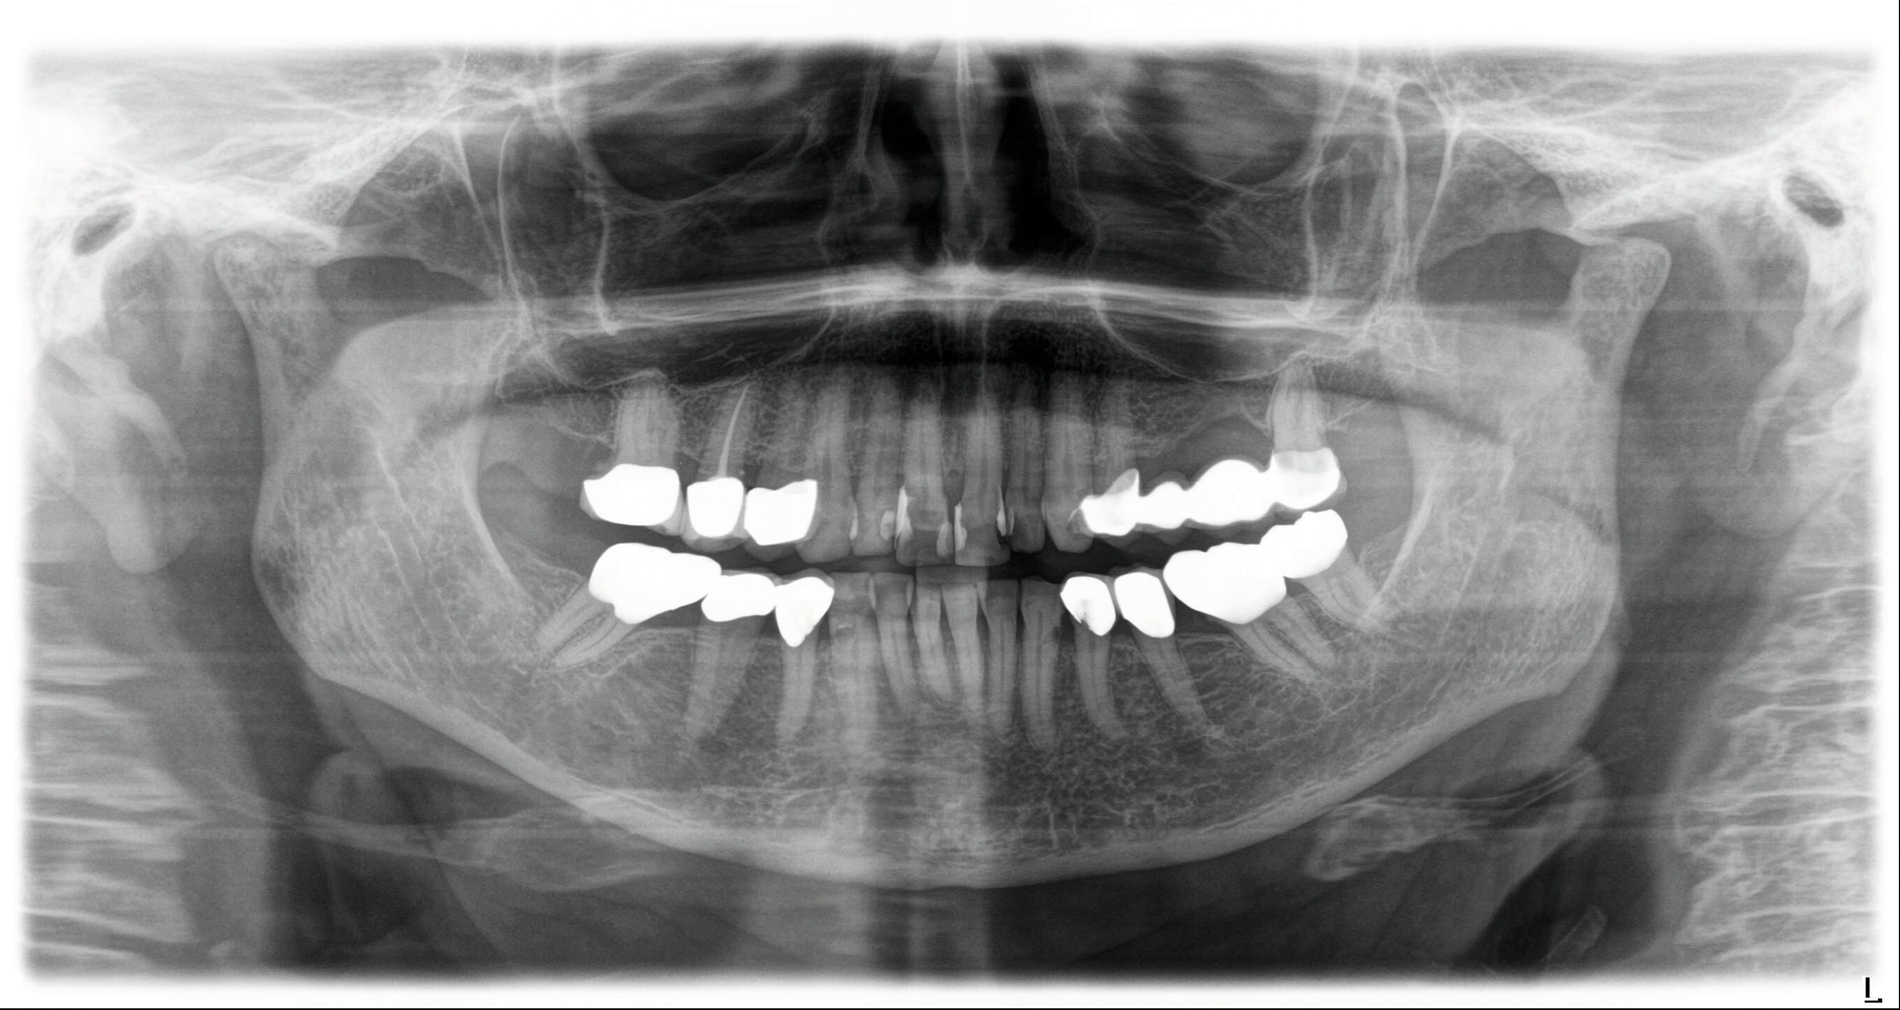

Hier wurde, neben einer klinischen Untersuchung, eine radiologische Diagnostik mittels OPG und DVT durchgeführt (Abbildung 3). Im Ergebnis manifestierte sich der dringende Verdacht, dass die überpresste Wurzelfüllung (Guttapercha-Stift/Sealer) die chronifizierte Pilzinfektion ausgelöst und unterhalten hatte. Daher wurde entschieden, den Zahn 26 zu extrahieren und gleichzeitig das überpresste Wurzelfüllmaterial zu entfernen.